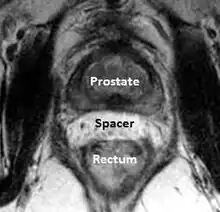

A new method to reduce rectal radiation injury in prostate cancer patients involves the use of an absorbable spacer placed between the prostate and rectum.

Such spacers are commercially available in some regions and are undergoing clinical trials in others.[30] By temporarily altering the anatomy these products have the potential to allow for improved cancer targeting while minimizing risk to neighboring healthy tissues. Prostate rectum spacers should be compatible with all prostate cancer radiotherapy treatments including 3D conformal, IMRT and stereotactic radiation and brachytherapy.